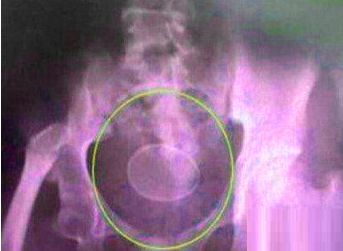

看似一枚普通的鸡蛋,原本不足为奇,但要说明其“出处”,就要让人大跌眼镜了。昨日,一对20出头的小情侣匆忙来到解放军411医院求医,问其原因,两人尴尬的脸红,无地自容。

据了解,就诊时,男子称女伴下腹沉重,感觉有异常东西,请医生帮忙查看。在随后的时间里,医生竟从女子的体内取出了一枚光滑的鸡蛋!在医生询问下,小情侣才支支吾吾地道出实情:

原来,在前一晚二人亲时,男子突发奇想,为了好玩便拿来了鸡蛋。女孩虽感觉奇怪,但在男友的一再要求下并未拒绝。谁知“请神容易送神难”,异物进去之后,再也不肯出去了,两人挤按、跳跃,勺子、筷子都用上了,仍无济于事,第二天便惊慌失措地赶到医院。

医院妇科医生告诉记者,所幸这枚鸡蛋已煮熟去壳,且在体内形态完整。“但如果不能及时取出,在人体36℃的温度下,鸡蛋极容易腐烂,加上体内细菌成分复杂,很快会发生霉变,造成感染。”医生说,“这个玩笑开得十分过火!希望情侣们在甜蜜时注意度,一味地追求刺.激可能会对身体和精神健康造成危害。”